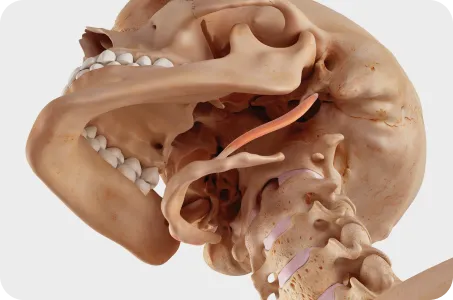

턱관절 교정의 핵심?

두개골과 경추를 함께 교정하는 것!

턱관절은 목뼈 1,2번 및 두개골과 함께 움직이기 때문에 턱관절에 문제가 생기면 목뼈과 두개골은 함께 틀어지게 됩니다.

따라서 턱관절 교정시 추나요법과 두개천골요법을 이용하여 목뼈 1,2번과 후두골, 측두골, 나비뼈를 동시에 교정하는 것이 치료효과를 높이고 재발률을 감소시키므로 한의학 치료가 꼭 필요합니다.

두개골 + 턱관절 + 상부 경추 (목뼈 1, 2번) 교정이 중요합니다.

우리 몸 중 움직임이 가장 많은 턱관절은 상부 경추 (목뼈 1,2번)를 중심축으로 움직입니다.

이 상부 경추가 틀어지면 후두골을 제대로 받치지 못하고, 두개골 또한 점점 틀어져 안면비대칭이 나타나게 됩니다.